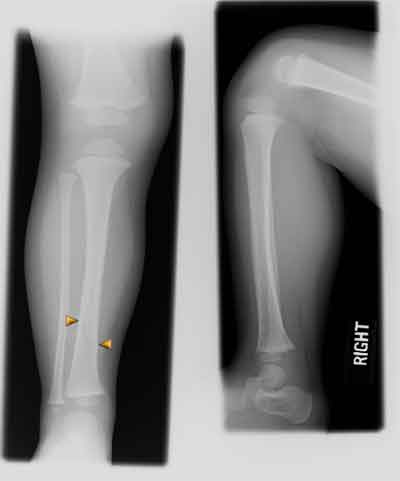

Totey Hoi Haddi